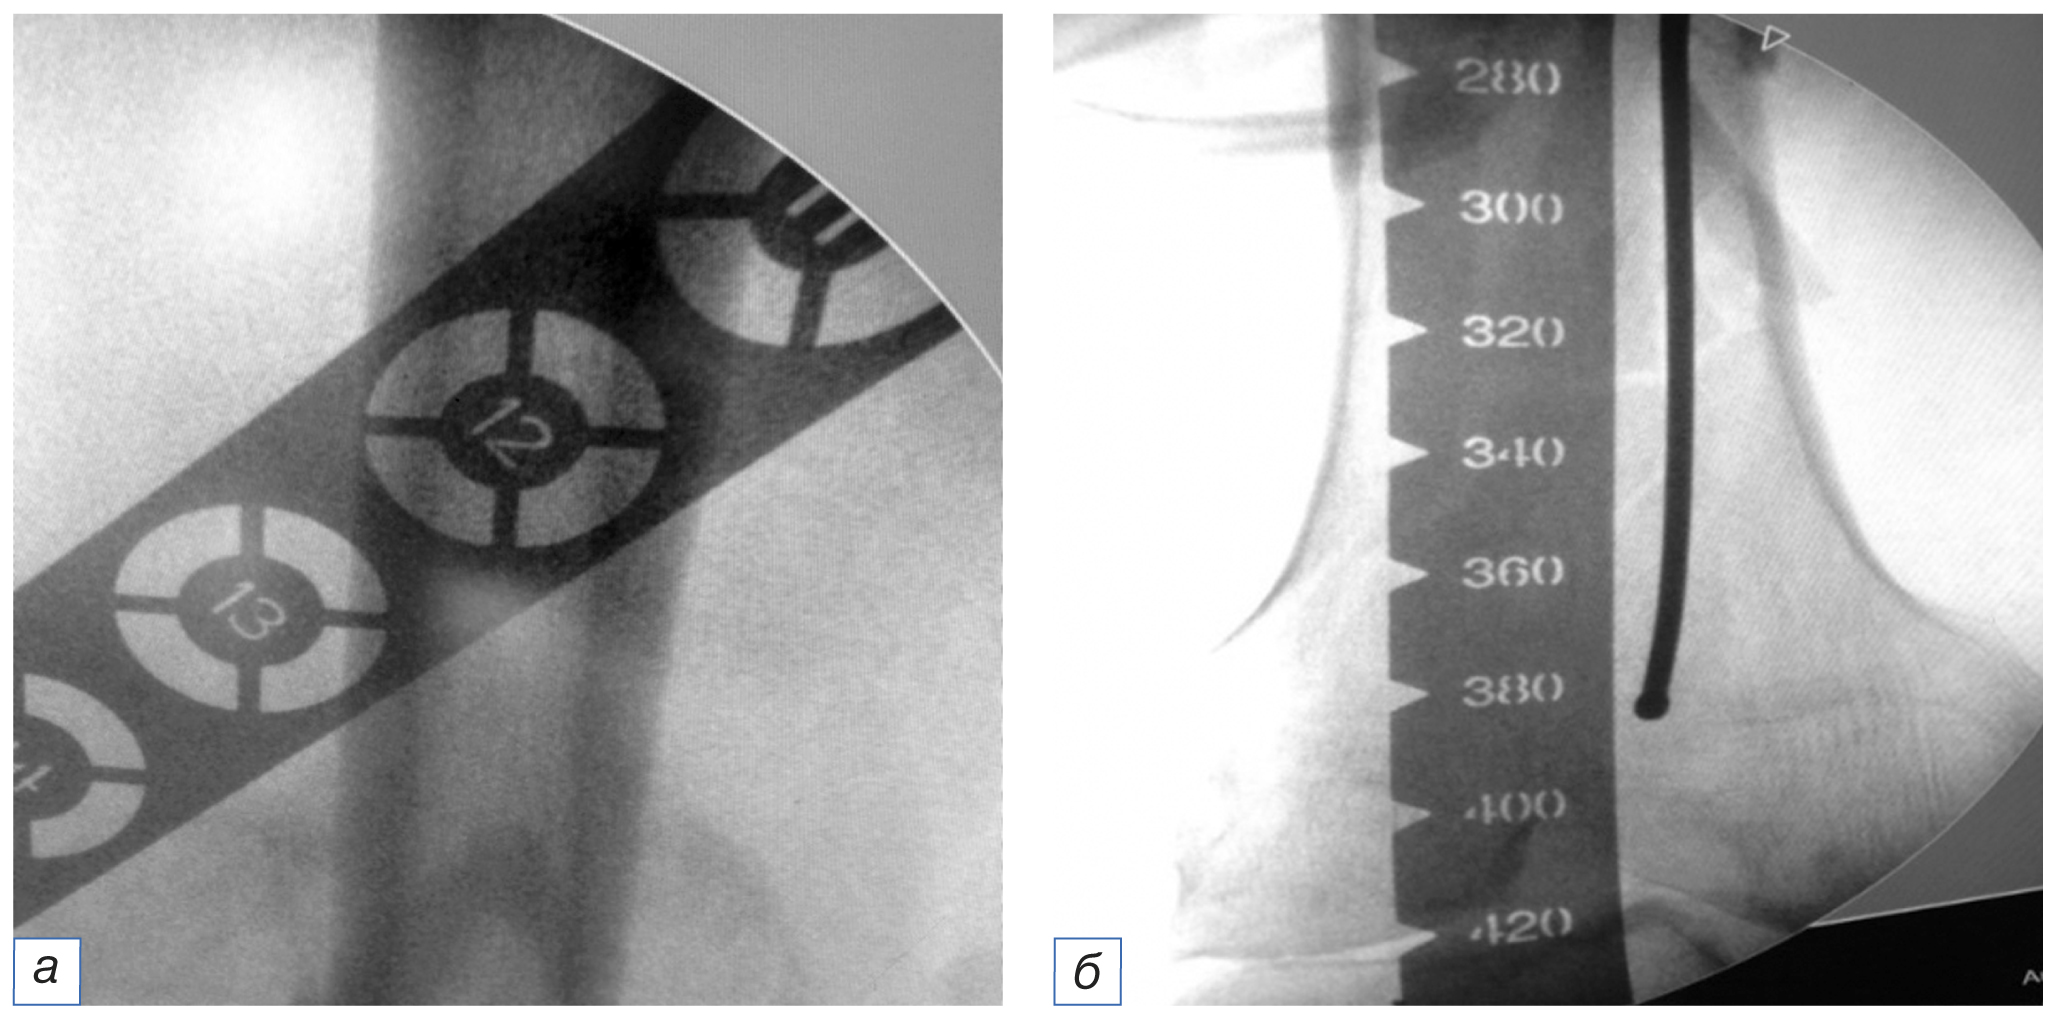

С учетом того, что после перелома, особенно при оскольчатом типе повреждения мыщелков бедра, достаточно трудно определить размеры штифта и винтов, используемых для остеосинтеза, в предоперационном периоде мы пользовались рентгеноконтрастной линейкой с целью уточнения ширины наиболее узкой части на дистальном отделе неповрежденной бедренной кости (рис. 2).

Рис. 2. Определение размеров требуемого фиксатора с помощью шаблонов (а, б). / Fig. 2. Determining the implant size with use of a template (а, б).